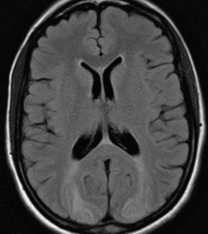

Abdominal computed tomography. Cystic lesion of the right lung. Courtesy Dr. V. Penopoulos.